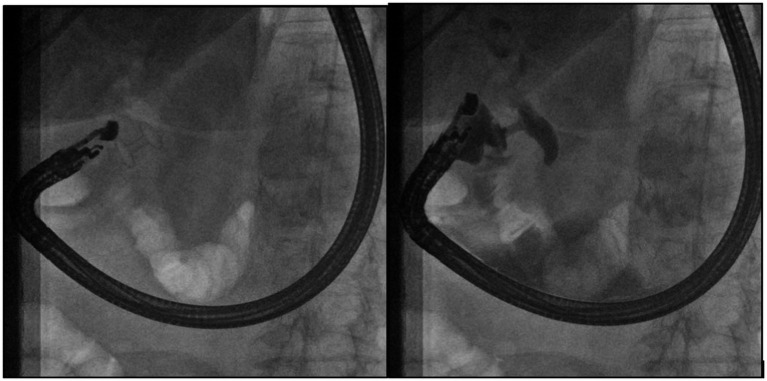

EUS-RV

We used a duodenoscope (TJF-Q190V, Olympus), a slim, linear ultrasound endoscope (EG38-J10EGU, Pentax Medical, Germany), and the Arietta 70 ultrasound system.

Under EUS guidance, the CBD was punctured with a 19-gauge EUS-guided FNA needle from either the stomach or the duodenal bulb. Following contrast injection in the CBD to confirm the correct position, a guidewire was passed into the CBD through the EUS needle and then manipulated through the papilla into the descending duodenum. The guidewire was then left in place, and a duodenoscope was maneuvered to the second portion of the duodenum; the wire was used to facilitate ampullary cannulation, and a conventional ERCP could then be performed.

EUS-BD

We used a slim, linear ultrasound endoscope (EG38-J10EGU, Pentax Medical, Germany) and the Arietta 70 ultrasound system. Under EUS guidance, a LAMS was deployed between the CBD lumen and the gastric or duodenal lumen. At the end of the procedure, the correct LAMS deployment was confirmed by contrast injection through the LAMS lumen into CBD (Figure 3).

We utilized AXIOS stent sizes of 8 mm × 8 mm and 6 mm × 8 mm.